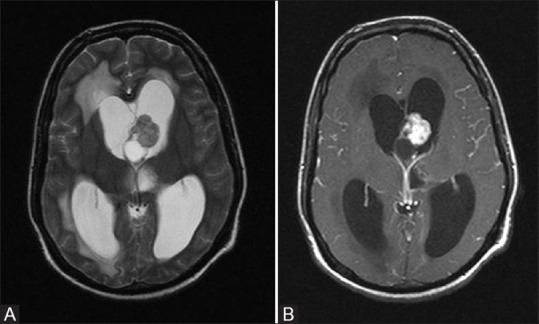

Phakomatoses or Neurocutaneous syndromes are a heterogeneous group of disorders and have variable inheritance pattern. Currently, more than 30 entities are included in this group. These disorders primarily affect the central nervous system; however, skin, viscera, and other connective tissues can also be involved with variable clinical presentation. We will describe and illustrate the various radiological findings of the common entities through the iconography of the cases presented to our department.

phakomatoses或神经皮肤综合征是一组异质性疾病,具有可变的遗传模式。目前,该组包括30多种疾病。这些疾病主要影响中枢神经系统;然而,皮肤、内脏和其他结缔组织也可能受累,临床表现各异。我们将通过提交至我科病例的影像学表现来描述和说明常见疾病的各种放射学表现。